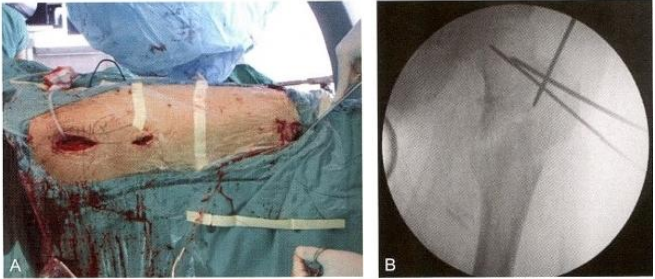

患者男,64岁。5年前患有脑卒中,影响右侧肢体,经康复治疗后 能够自己行走,但肌力略差。此次在平地上跌倒,发生右侧股骨转子间 骨折。入院后经术前检查,诊断为小转子二分型的二部分股骨转子间骨折,属于难复位类型。第二天在骨科牵引床上进行头髓钉内固定手术。

术中在肢体松弛的状态下,从螺旋刀片打入的切口插入器械进行复位。在手指的扪摸指引下,先用骨钩解除外上角的骨性交锁,再用剪刀 剪断紧张的骼股韧带和骼肌腱,解除软组织嵌顿造成的弹性交锁。在手 指的感知下牵引和旋转肢体,用骨钩牵拉头颈骨块下方的尖齿,头颈骨 块与股骨干即能获得满意的复位(对线、皮质对位)。再按常规操作,完 成闭合插钉内固定。

术毕透视,示骨折复位质量优(4分),内固定稳定性优(8分)。术 后三维CT 证实前内下角获得骨皮质对骨皮质的可靠支撑。术后1周,患 者在搀扶下可下地负重站立,练习行走。随访1.5年,骨折完全愈合(图 9-21)。

图9-21 小转子二分型难复位骨折。A.术前X 线片示股骨转子间二部分骨折,小转 子被骨折线平均分为上下两块,分别与头颈骨块和股骨干相连;B. 外上角骨性交锁 (箭头);C.三维CT重建图像,显示典型的移位特征:头颈骨块屈曲外旋,股骨干上 移短缩,头颈骨块下方骨皮质尖齿骑跨于股骨干前方

图9-21 ( 续 )D. 采用Mimics 软件模拟骨折复位,显示小转子从中部平分为上下两 块 ;E. 骨折移位特征示意图;F. 在打入股骨头导针和螺旋刀片的过程中,牵拉骨钩维 持复位;G 、H. 术毕正、侧位透视影像,示骨折复位良好,内固定位置满意;I 、J. 术 后1周随访X 线片;K 、L. 术后三维CT 显示前内下角骨皮质相互抵住、支撑(箭头), 稳定性优良,允许患者早期下地站立行走。★为小转子上半部骨块,从头颈骨块的下 方骨皮质尖齿上游离脱落,由于腰大肌的牵拉而向前向上移位。M、N. 术后随访1.5 年,骨折完全愈合